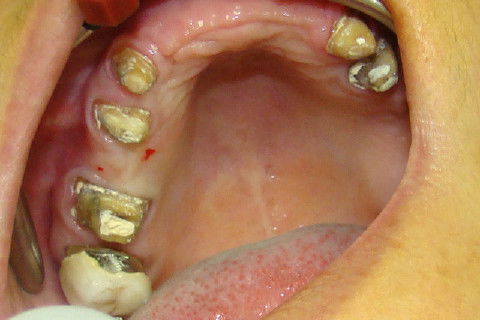

Colocação de proteses temporarias superiores enquanto aguardamos o tratamento ortodontico

Retorno da paciente após o tratamento ortodontico

Finalização do tratamento reabilitador, com coroas metalo-ceramicas superiores e coroas unidas no lado direito da mandibula e unitaria da lado esquerdo